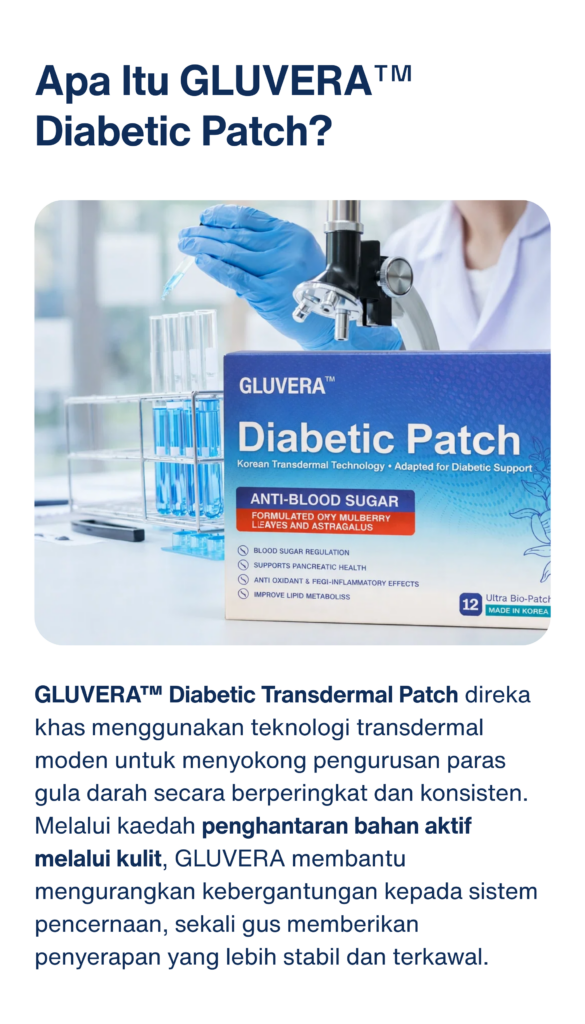

Adakah GLUVERA™ membebankan perut atau buah pinggang?

Tidak. GLUVERA tidak perlu ditelan, membantu mengurangkan beban pada sistem pencernaan dan organ dalaman.